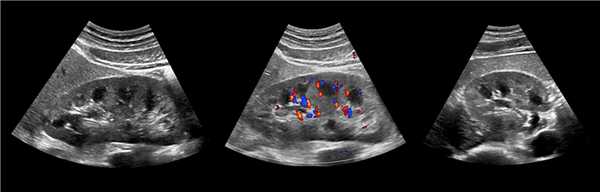

Клинический пример из первой группы. Пациент М., с хронической почечной недостаточностью. Трансплантация почки произведена от живого родственного донора. Трансплантат находится в правой подвздошной области. При нормальном функциональном состоянии трансплантата, показатели цветовой и спектральной допплерографии оценивались как удовлетворительные, с индексом резистентности не более 0,60 (рис. 1); показатели жесткости паренхимы почечного трансплантата при УЭСВ на различных участках составили от 20,05 до 29,18 кПа (рис. 2-4).

Рисунок 2. Исследование в режиме ультразвуковой эластографии сдвиговой волны у пациента М.: жесткость паренхимы в зоне медиального края трансплантата 19,8 кПа

Рисунок 3. Исследование в режиме ультразвуковой эластографии сдвиговой волны у пациента М.: жесткость паренхимы в зоне верхнего полюса почечного трансплантата 21,4 кПа

Рисунок 4. Исследование в режиме ультразвуковой эластографии сдвиговой волны у пациента М.: жесткость паренхимы в зоне нижнего полюса почечного трансплантата 16,8 кПа

У пациентов второй группы, при нормальных показателях клинико-лабораторных и допплерографических исследований, показатели жесткости почечного трансплантата составили 17,00-26,06 кПа.